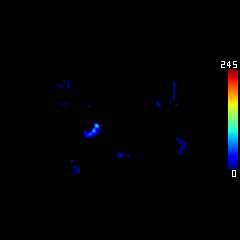

DeepClue-Precise CT 측부혈류영상

Perfusion CT를 이용한 측부혈류영상

후기정맥기

지연기